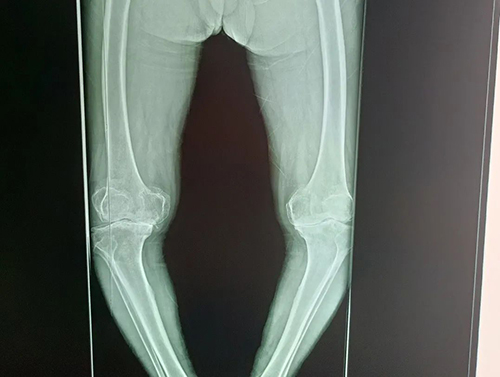

近一年以来,症状加重,沈爷爷膝关节站立、行走均受限,膝内翻明显。来院就诊后确诊为“双膝骨性关节炎”。

沈爷爷关节疼痛时间久,在我院行X线片显示膝关节间隙非对称性狭窄、内翻畸形明显、关节不稳。我院骨科专家分析沈爷爷情况后认为目前患者骨结构改变,保守治疗无效。与患者家属说明详细情况后,排除手术禁忌,决定为其行“全膝关节置换术”,分两次进行。目前,沈爷爷恢复良好,正在康复中。